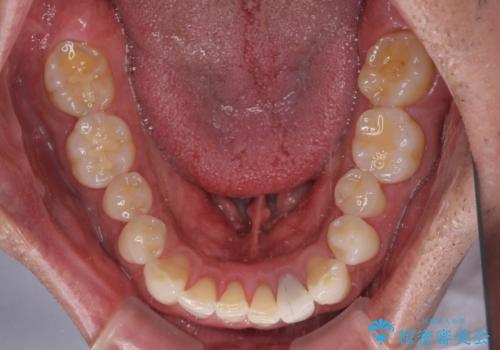

内側にある歯が干渉する 上顎前歯の部分矯正

- 上顎の前歯が内側にあり、下顎のセラミッククラウンと干渉することが気になるとのことで来院された患者様です。

上顎前歯にワイヤー装置を装着し、セラミッククラウンとは干渉しないようにしながら歯列を整えることとしました。

セラミッククラウンとの干渉はすぐに改善され、歯列も整いましたが、一方で、前歯で食事が噛みにくくなり、1年近い治療期間となりました。